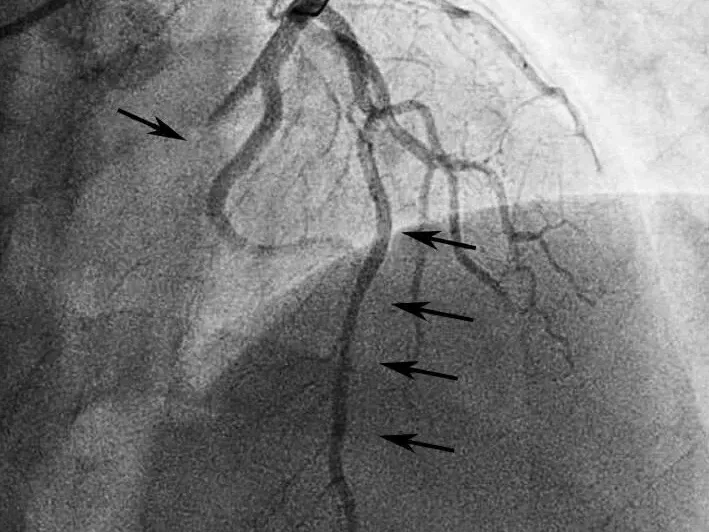

给予双联抗血小板、调脂、控制心率、抗心衰及泼尼松龙60mg每日1次,并皮下注射依诺肝素强化抗凝,1周后复查心脏超声(图2),发现右房内疑似血栓影完全消失,患者也无低氧、咯血等肺栓塞临床表现。后完成CAG +光学相干成像(OCT)检查(图3),提示:左优势型,前降支近段管腔不规则发白,考虑血栓影,管腔分支稀少,血流TIMI 3级;回旋支远段节段性狭窄达90%,血流TIMI 2级;右冠细小。

图3 冠脉造影结果

A图显示前降支血流稍慢,中段可见管腔发白,怀疑血栓影;B图提示回旋支远段重度狭窄90%,血流TIMI 2级